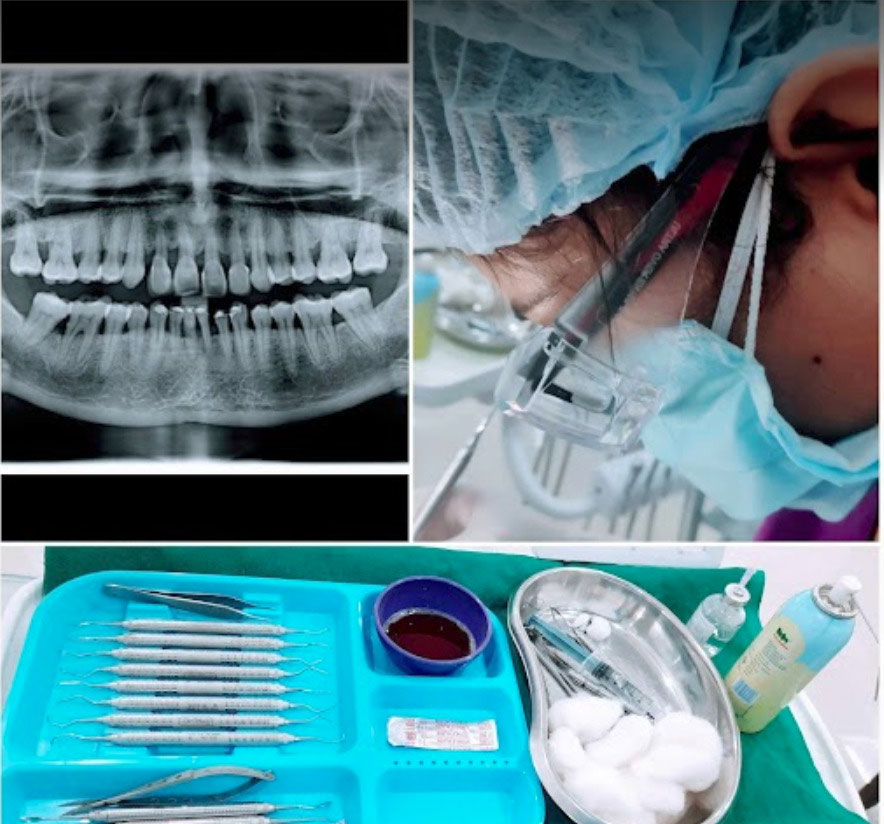

General dentistry involves the evaluation, diagnosis, prevention, and treatment of diseases & conditions of the body’s oral and maxillofacial region.

If the tooth extraction process required any soft tissue (gum) or bone removal then it will be considered as a minor surgical process.

We provide the best measurements to give our patients a smooth experience of painless tooth extraction & advicing all post operative instructions.